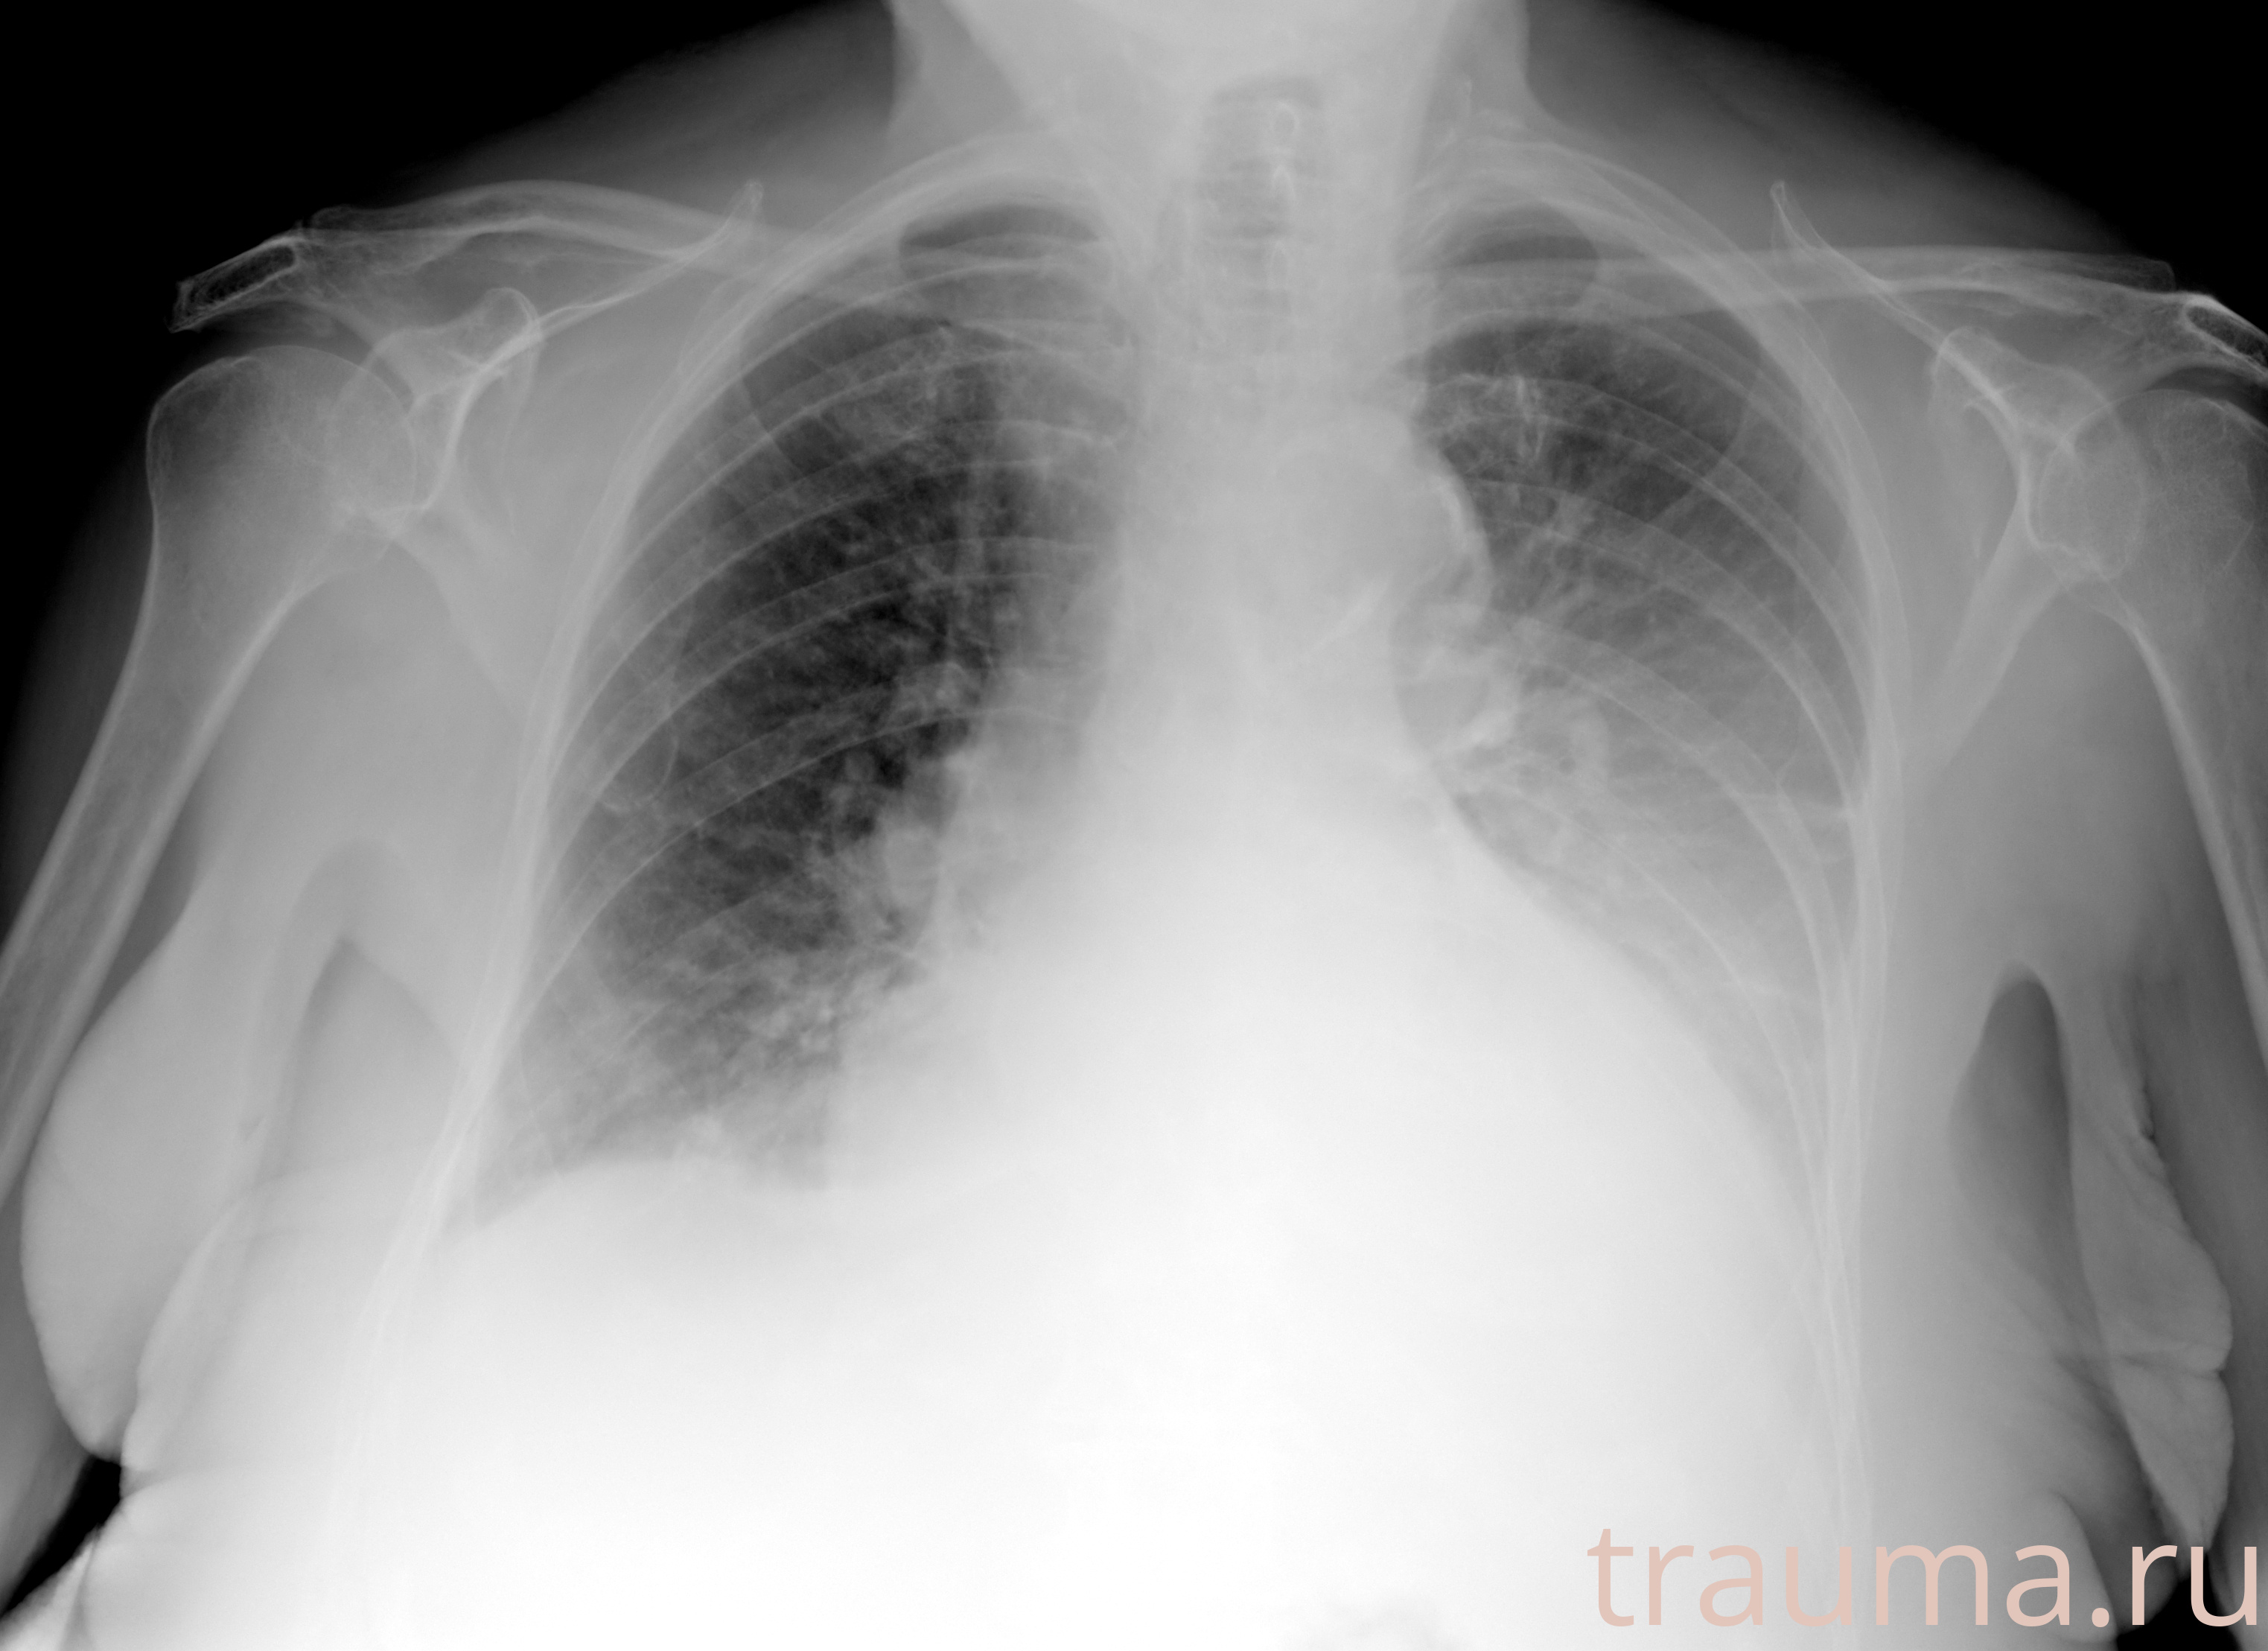

Рентген на дому: по вашему адресу приезжает врач-рентгенолог, травматолог-ортопед с мобильным рентгеновским аппаратом, проводит диагностику травмы или заболевания, делает необходимые рентгенограммы, дает рекомендации по дальнейшему лечению. Получить качественные снимки в домашних условиях возможно благодаря уникальной методике, разработанной МосРентген Центром для института  Склифосовского

при переломе шейки бедра и пневмонии от компании МосРентген Центр - партнера Института имени Склифосовского